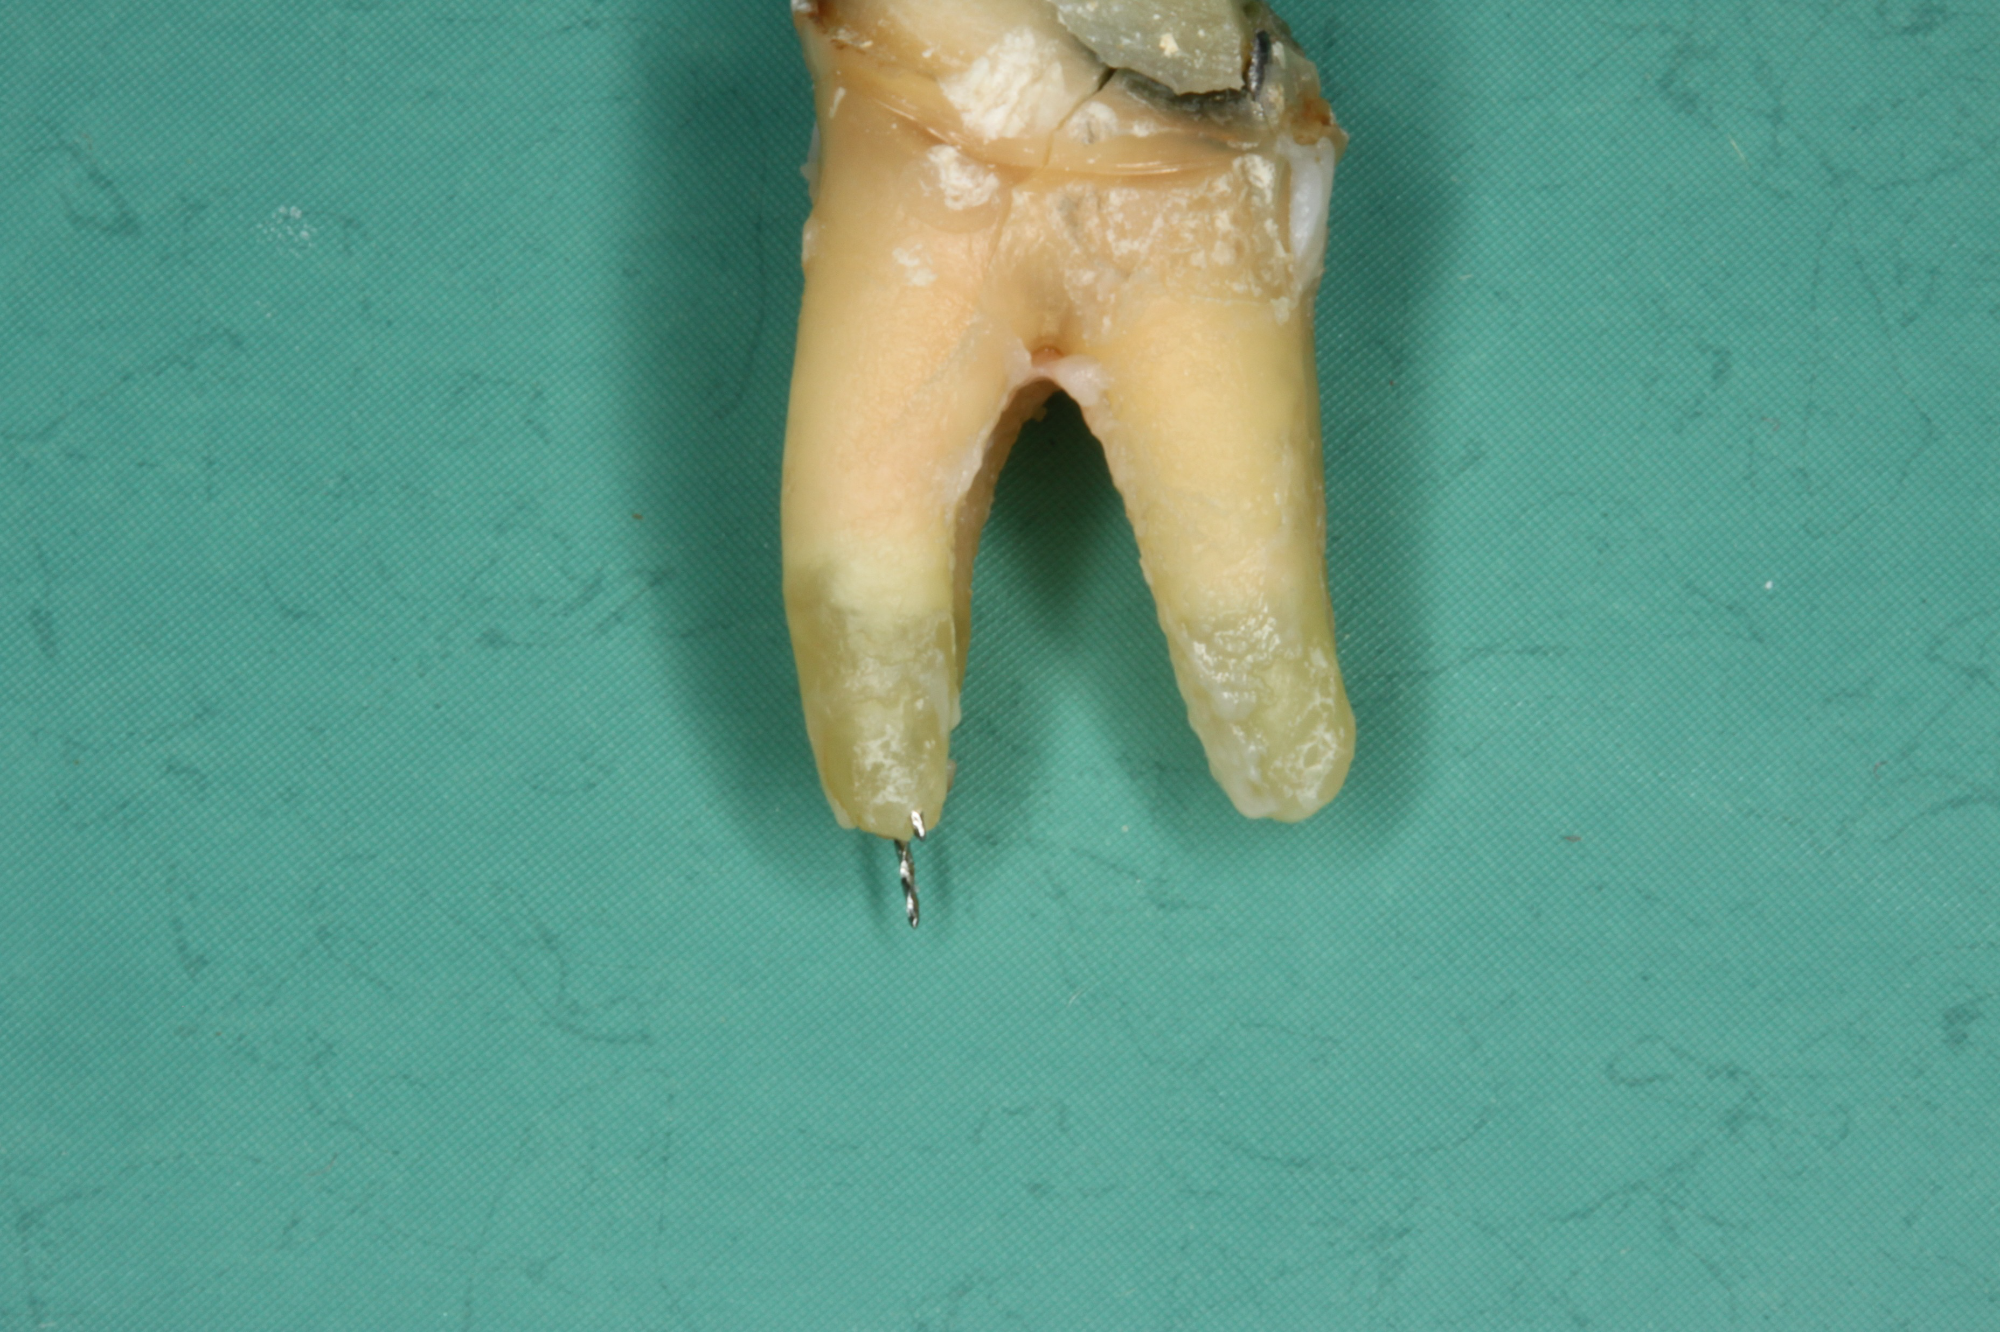

Wurzelkanalbehandelte Zähne sind tote Zähne! Auch die beste Mikro-Endodontie wird kaum eine komplett bakteriendicht abgeschlossene Wurzel realisieren können. Akzessorische Seitenkanäle und die Endo-Paro Verbindung über die Dentintubuli bleiben bestehen.

Technische Limitation

Pro Quadratmillimeter Wurzeldentin befinden sich 40 bis 60 tausend Dentinkanälchen, welche sich dann auf eine Länge von etwa 1 – 5 km summieren.

Die Entfernung wurzelkanalbehandelter Zähne in unserer Praxis

Der Austausch wurzelbehandelter und toter Zähne erfolgt so schonend wie möglich. An die Stelle des toten bzw. wurzelbehandelten Zahnes wird direkt in derselben Behandlung ein Keramikimplantat gesetzt, wenn genug gesunder Knochen vorhanden ist.